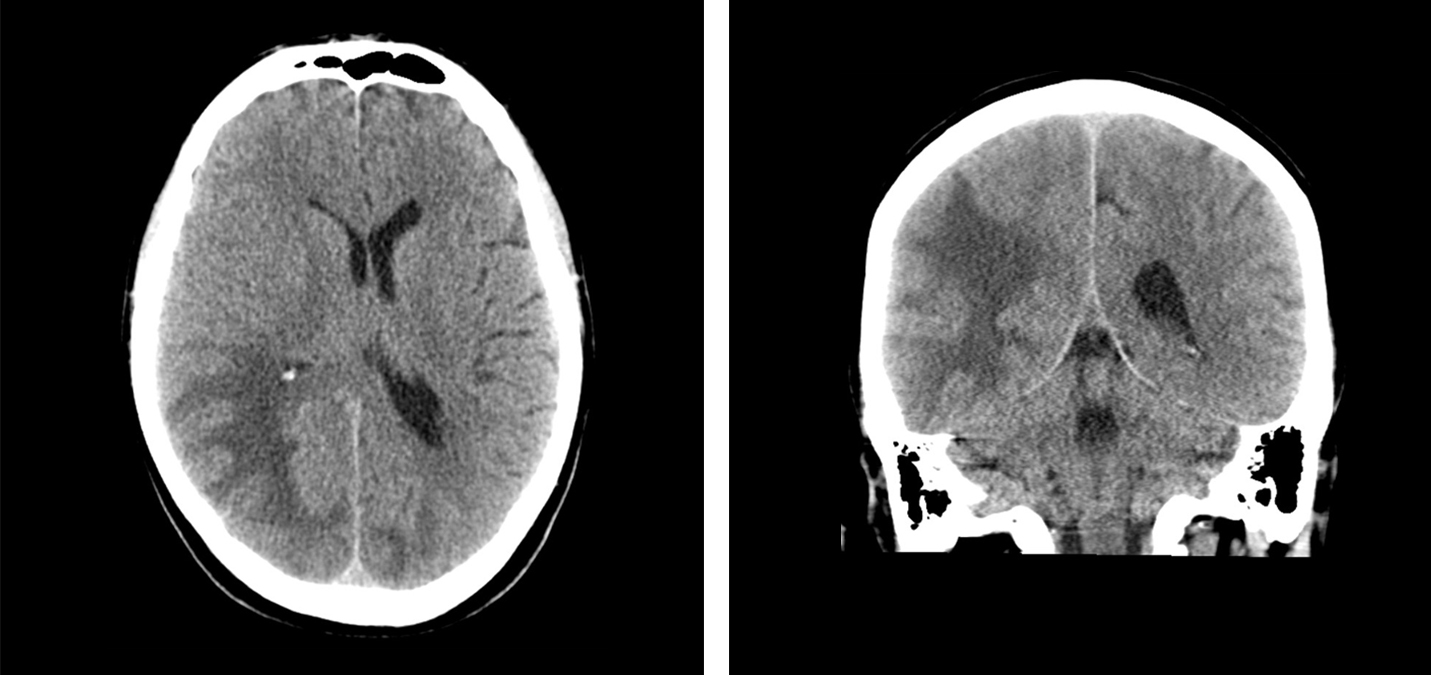

Pasienten ble undersøkt med CT caput uten og med intravenøs kontrast. Det ble sett lavattenuasjon, som ved ødem i hvit substans oksipitalt, mest uttalt på høyre side med masseeffekt og midtlinjeforskyvning mot venstre (fig 1).

Ved øyelegeundersøkelse ble det konkludert med homonym kvadrantanopsi (synsfeltsutfall i begge nedre venstre kvadranter), ellers normale funn. På bakgrunn av uttalte trykksymptomer og påvist hjerneødem på CT mistenkte man primært hjernemetastaser, og det ble derfor startet behandling med høydose perorale kortikosteroider. Pasienten ble henvist til MR caput grunnet fortsatt mistanke om hjernemetastaser.

MR caput med intravenøs kontrast (fig 2) viste økt signal i hvit substans i høyre temporal- og oksipitalregion samt i mediale venstre oksipitalregion ved T2-vekting og FLAIR-sekvenser. Det var ingen restriksjon på diffusjonsvektet serie (vanlig ved hjerneinfarkt, abscess og i svulster), men økt ADC-verdi (apparent diffusion coefficient). Dette tydet på økt vanninnhold i hjernevevet, best forenlig med et vasogent ødem. Det var ingen patologisk kontrastoppladning eller kontrastladende lesjoner, noe som talte mot metastaser, abscess eller primær hjernesvulst, men man så tallrike punktformige blødninger i cortex i de aktuelle områdene på suceptibilitetsvektet sekvens. MR-spektroskopi viste normal metabolittfordeling, som også talte mot tumor.

Ut fra sykehistorien, sykdomsforløpet og MR-funn med vasogent ødem og multiple kortikale småblødninger i oksipitalregionene, vurderte vi at diagnosen posterior reversibel encefalopati-syndrom var mest sannsynlig, forårsaket av tumorrettet behandling med regorafenib.